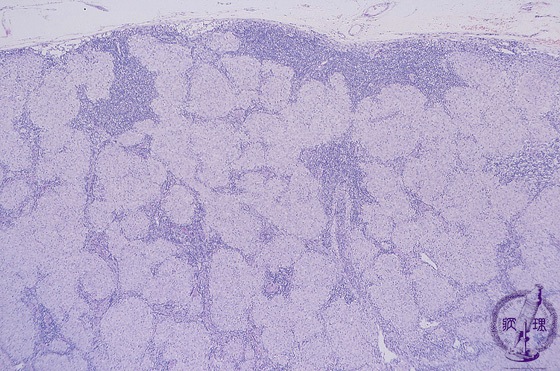

Microscopic image (H&E low power view): Within lymph nodes, numerous pale pink epithelioid histiocytes are seen in band like and nodular formations. Nodules are of relatively uniform size.